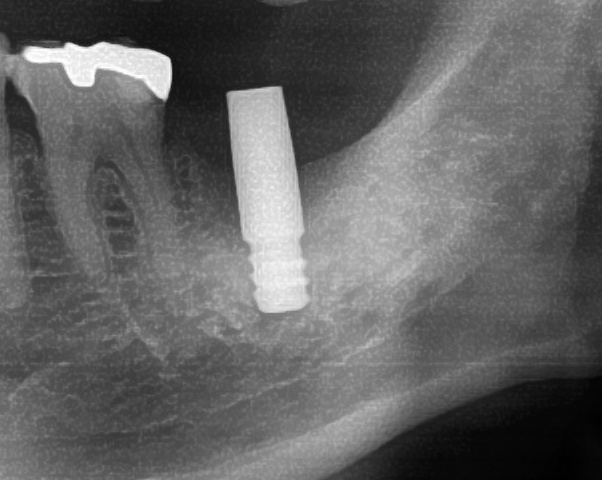

開けた穴に、専用道具を使ってネジを締めるように長さ2センチ程のインプラントを骨に埋め込んでいきます。

しっかりとインプラント埋め込まれた後は、動揺がないか、噛んだ時に当たらないかなどを確認して、最後にパノラマ写真を撮影して今回のオペは終了となりました。